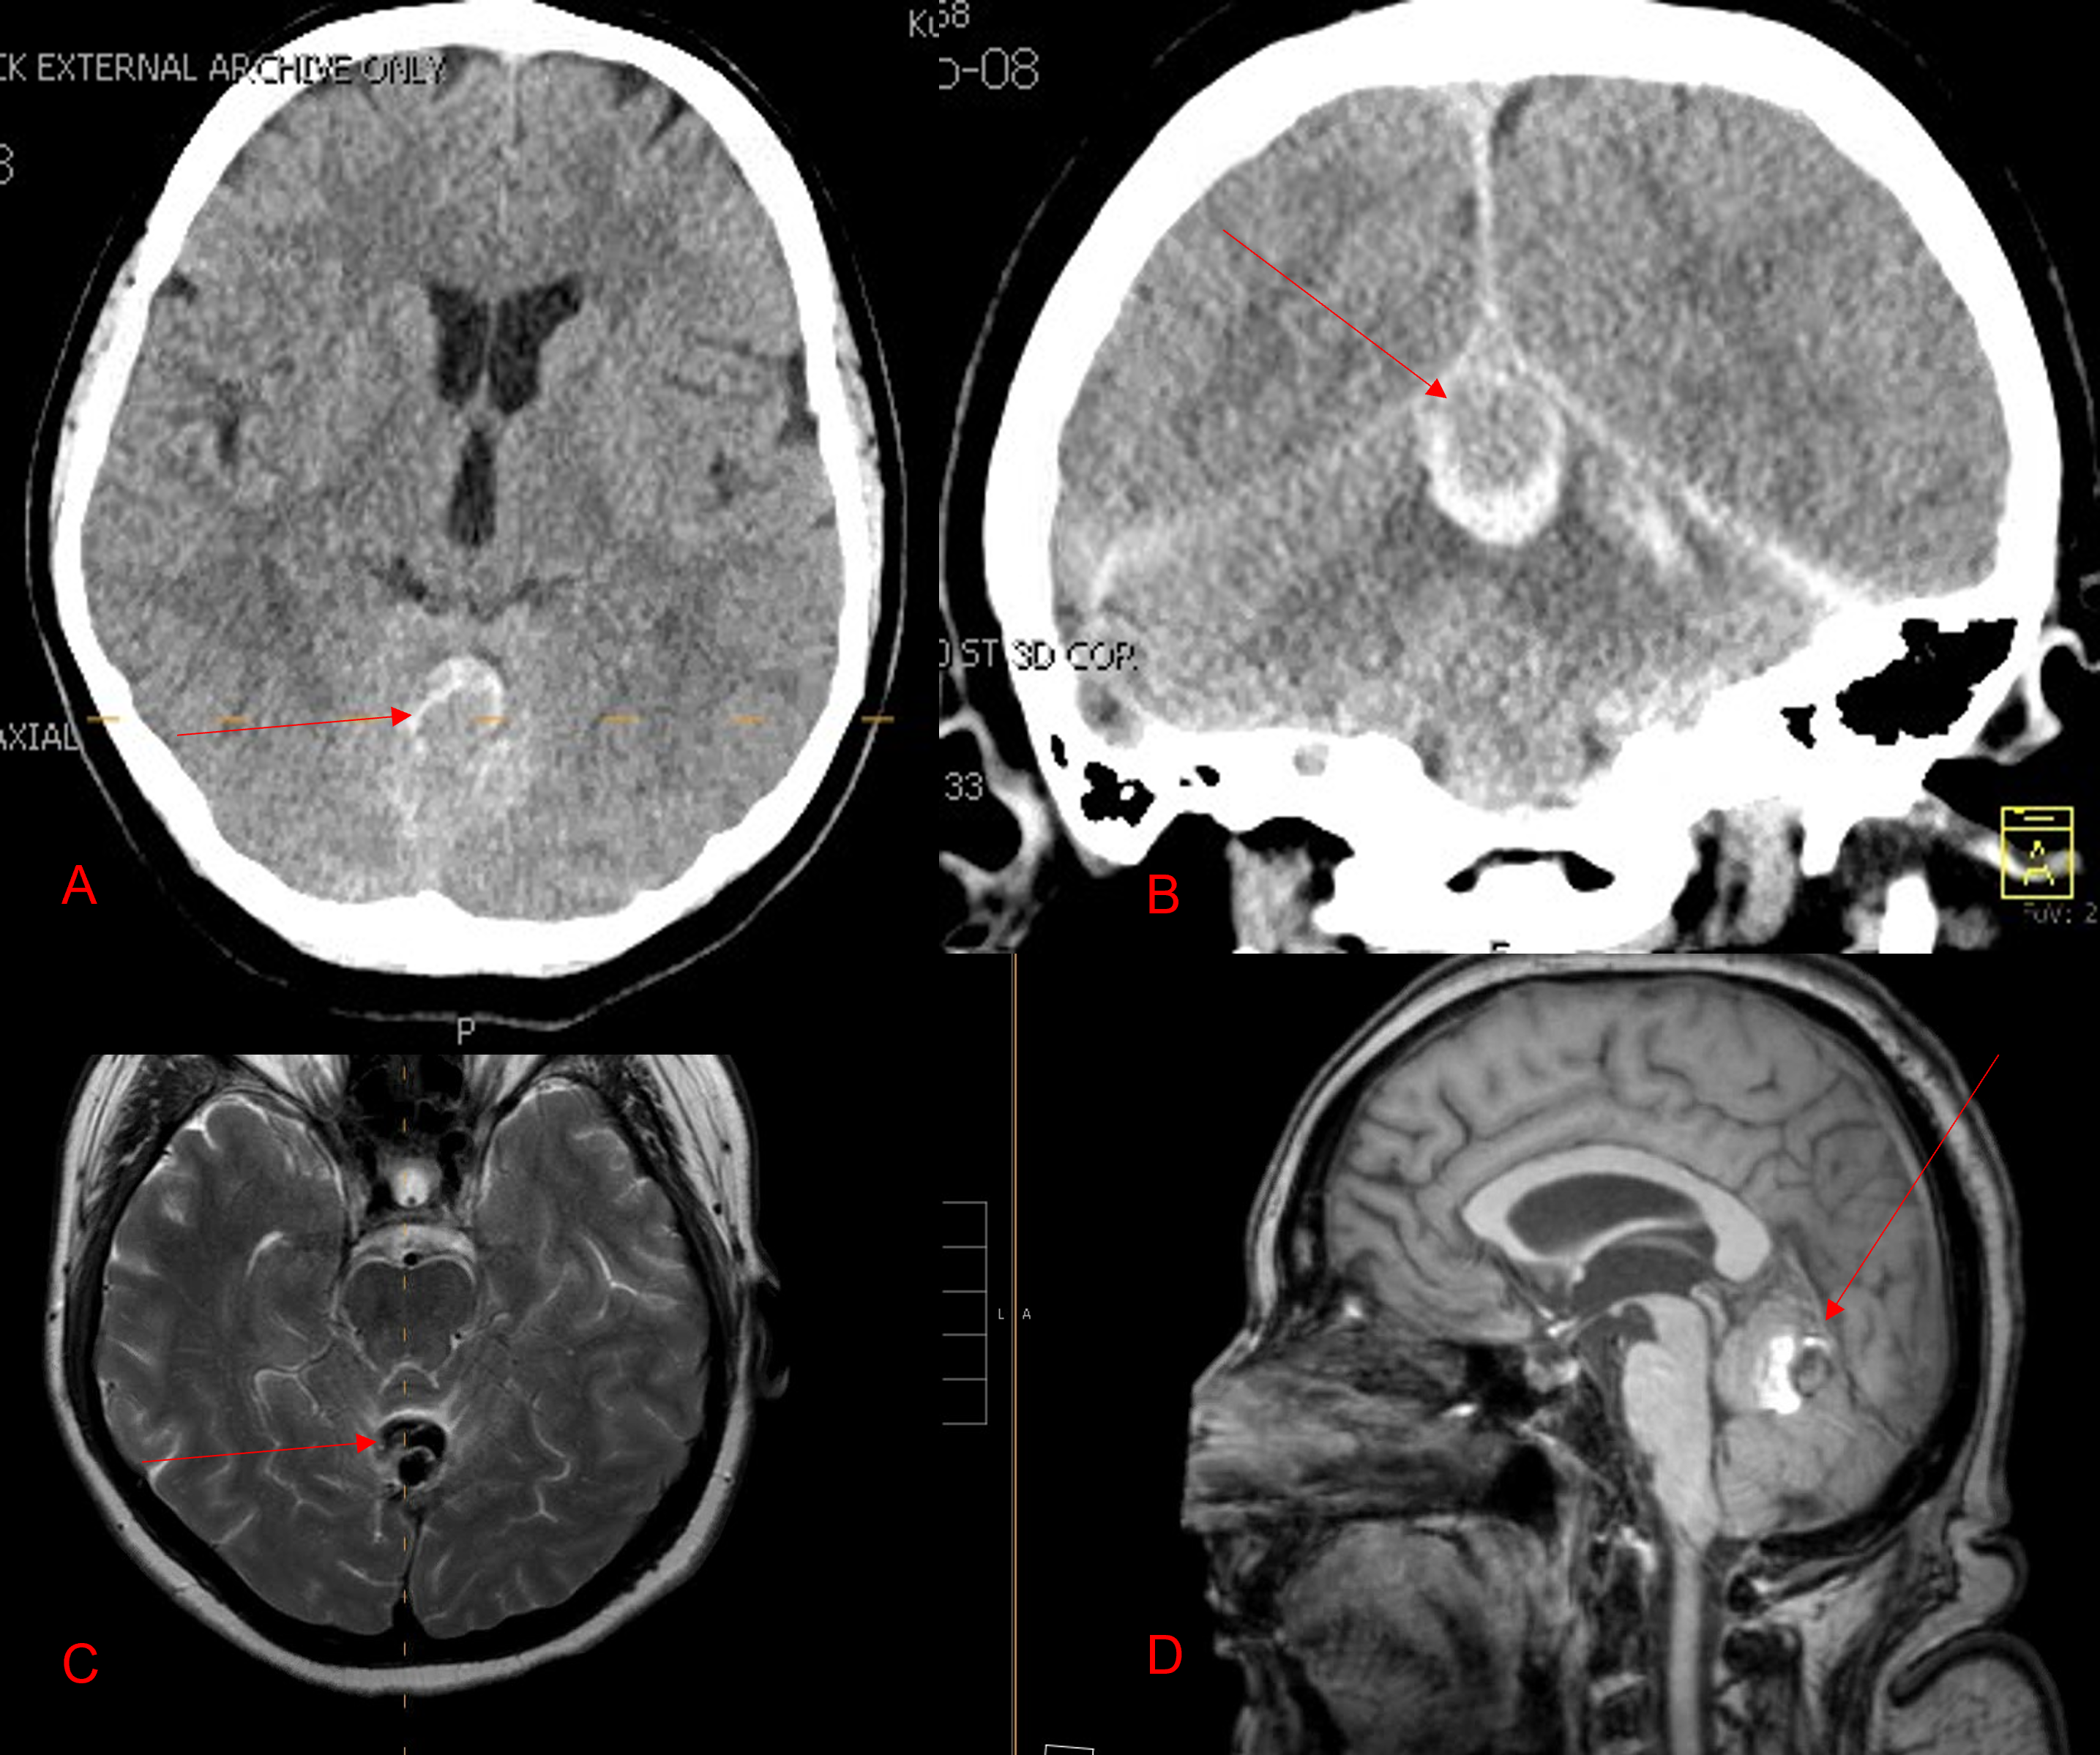

The patient agreed to receive minimally invasive treatment with Bilateral Middle Meningeal Artery Embolization, a new approach to promote resorption of chronic and subacute subdural hematomas in patients that are not improving with conservative measures or have contra-indications to surgical evacuation. Selective catheterization of the Middle Meningeal Artery is followed by transarterial embolization of the territory and inflammatory membranes that are felt to be secreting serosanguinous proteinaceous exceeding the capacity for resorption. MMA embolization was performed bilaterally in this patient. (Figure 2. A and B)

Figure 2. A) Initial right ECA angiogram ; B) Post MMA Embolization; C) Selective Embolization Of Middle Meningeal Artery Membranes using PVA particles (arrows).

CT follow-up at 1 week demonstrates early resorption. 2 weeks post MMA embolization, resolution of the left subdural collection with new small thin acute hemorrhage in an otherwise stable right subdural collection is observed (Figure 3. A and B).

Figure 3. A) 1 week post MMA embolization demonstrating decreasing thickness bilaterally B) 2 weeks post MMA demonstrates resolution on left, with small new acute component on right with overall decreased thickness.